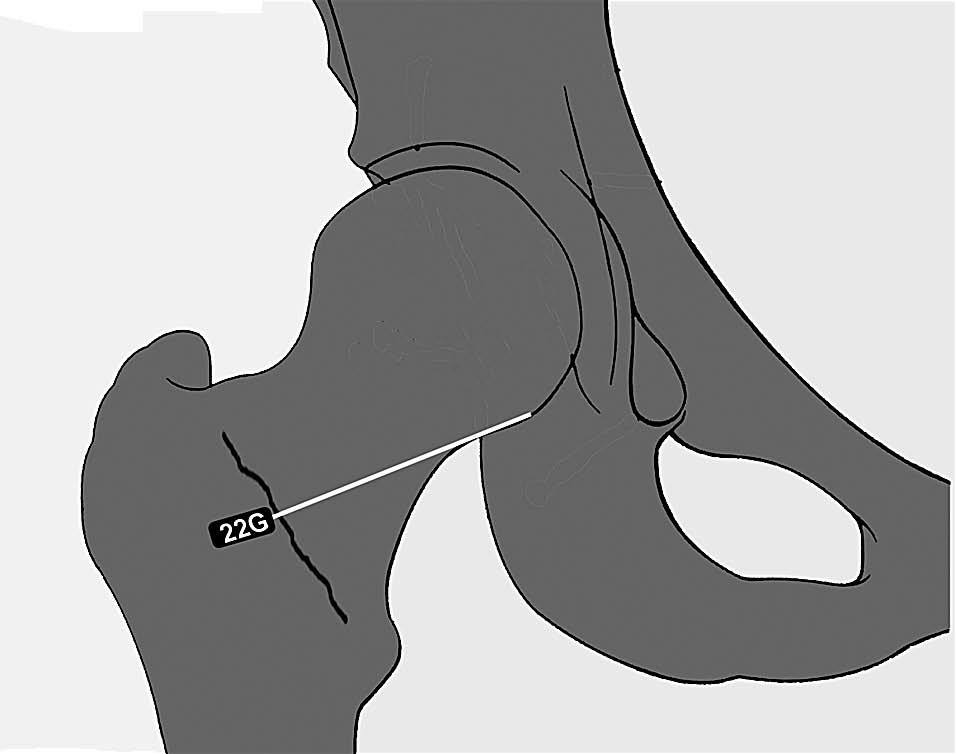

La punción articular se realiza con control fluoroscópico con el paciente en decúbito supino y la pierna extendida con ligera rotación interna. Previamente a la punción es aconsejable palpar la arteria femoral y marcar en la piel su situación. El punto de punción se sitúa en la zona media de la línea intertrocantérea, dirigiendo la aguja directamente hacia la región inferior de la unión entre cabeza y cuello femoral (fig. 1). Se confirma la localización intraarticular de la aguja con una pequeña cantidad de contraste yodado que inmediatamente dibuja los recesos capsulares y el ligamento orbicular. La punción se realiza con una aguja espinal de 22 G. Se inyecta una cantidad de la dilución de gadolinio que oscila entre 10 y 20 ml.

Fig. 1.--Dibujo que ilustra la vía de punción de la articulación de la cadera. Se pincha a nivel de la zona media de la línea intertrocantérea, dirigiendo la aguja con ligera inclinación craneal hacia la región inferior del cuello femoral.